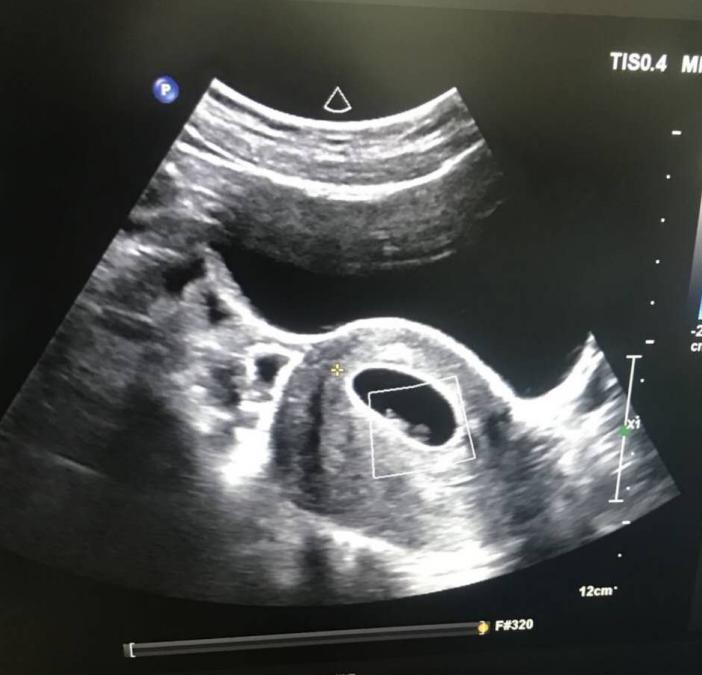

我还是建议做手术,在我院又一次做了宫腔粘连分离手术,手术很顺利,术后我给予中西药和物理结合调理了四个月,徐丹发现之后的每次月经来潮,经量都要比之前多一些,这是好兆头,说明宫腔粘连的创面内膜已慢慢爬行生长,只有内膜铺满了整个宫腔,才不会出现宫腔的再次粘连,患者才有怀孕的可能。再次复查彩超内膜恢复挺好,就开始指导他们自然怀孕,术后的第六个月,患者终于如愿怀孕了。